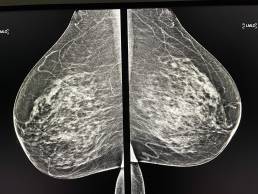

67-year-old woman, screening mammogram.

MammoScreen® points to an irregular, pleomorphic microcalcifications cluster, located in the deep retro areolar region of the left breast.

Ultrasound-guided macrobiopsy with clip placement confirms SBR II, Her2+ invasive carcinoma.